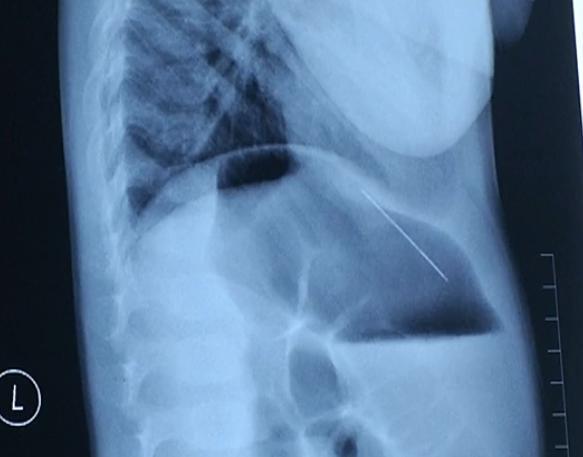

拍片发现,孩子肝脏里面有个金属异物,外表就是根针,从片子上看,大概有四公分!

这可不得了,这根针有可能继续游走,如果走到大动脉,心脏边上刺破血管,将会大出血,引起生命危险!

医生决定立即手术取针,这根针的位置,在肝脏距离心脏的位置非常近,手术难度不小。